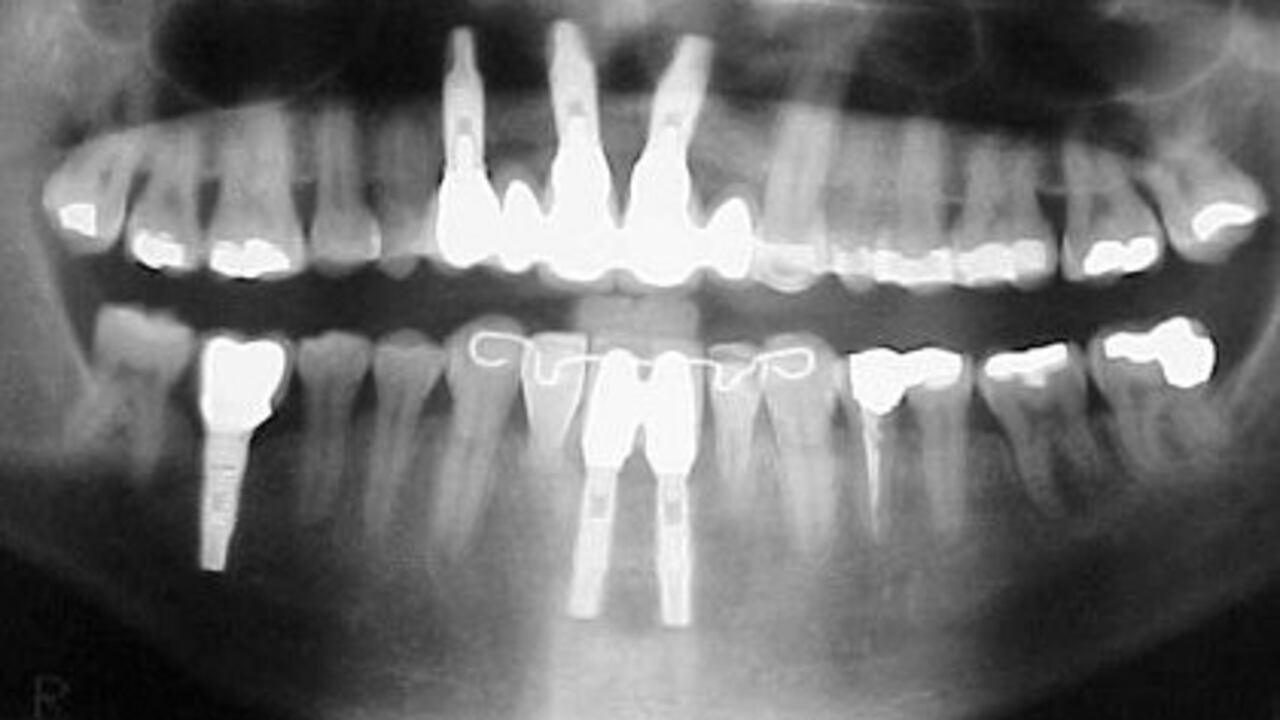

El estudio encontró asimismo una vinculación entre el riesgo de meningioma y los rayos X panorámicos, que se usan con menos frecuencia y se toman desde afuera de la boca y dan una visión de todos los dientes superiores e inferiores.

Un tipo de rayos X que se ha usado en los exámenes dentales parece estar vinculado con la forma más común de tumor cerebral, que casi siempre es benigno pero puede ser muy debilitante, según un estudio publicado por la Sociedad Estadounidense del Cáncer.

El estudio encontró en un nivel general que las personas con esos tumores, conocidos como meningiomas, tenían dos veces más probabilidades que las personas sin tumor cerebral de haberse sometido alguna vez en su vida al examen de rayos X, en el cual el paciente sujeta una película en sus dientes.